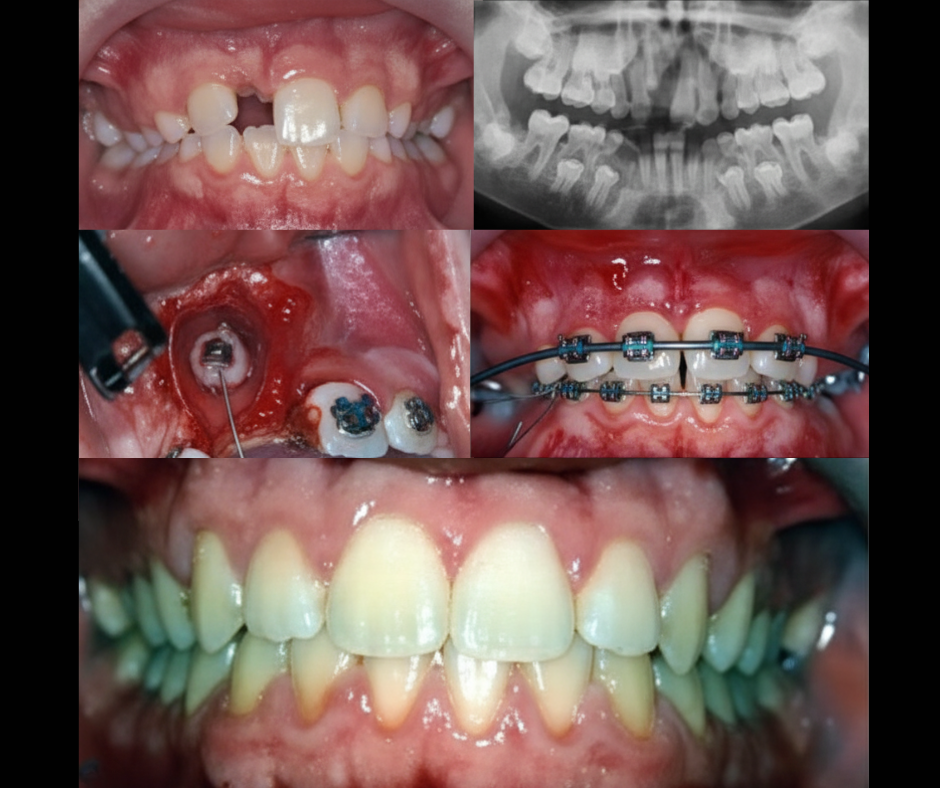

COLOCACIÓN DE BOTONES (BRACKETS) EN DIENTES INCLUIDOS

Ayudamos a que tus dientes erupcionen correctamente, de forma segura y guiada

Cuando un diente no puede salir por sí solo porque está incluido (generalmente caninos), usamos una técnica ortodóntica moderna llamada colocación de botones.

Este procedimiento permite traccionar el diente suavemente hasta llevarlo a su posición correcta dentro del arco dental.

¿Cómo funciona?

Después de una pequeña apertura realizada por el especialista, se coloca un botón especial sobre el diente incluido.

Este botón se conecta a tus brackets o alineadores, permitiendo que el diente se mueva de forma controlada y progresiva hasta llegar a su lugar.

Es un procedimiento rápido, seguro y completamente planificado, pensado para proteger tus dientes y tejidos.

Tracción suave y controlada

Mayor predictibilidad del movimiento

Resultados estéticos y funcionales

Acompañamiento en cada fase del proceso

Recupera la armonía de tu sonrisa

Si tienes un diente que no ha erupcionado, existe una solución ortodóncica efectiva y moderna para ayudarte.